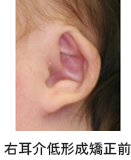

3. 耳介

妊娠の2ヵ月から3ヵ月の時に6つの膨らみが頚の位置にできて、徐々に耳の形ができてきます。標準的な耳の形は縦横の比率が2:1と縦が長く、縦の長さは成人男性では65㎜前後、成人女性では60㎜程度とされています。 しかし、耳の形や大きさは人によりさまざまで、全く同じ顔の人がいないのと同様に全く同じ形耳の人もいないと言っても過言ではありません。

乳児の耳介は可塑性があるため、歯の矯正と同様に耳介も矯正治療ができる事がはっきりしてきました。耳の矯正治療は本人が嫌がって外そうとする手の動きができるようになる前の生後3ヵ月以内が最も効果的です。

乳児の耳介は可塑性があるため、歯の矯正と同様に耳介も矯正治療ができる事がはっきりしてきました。耳の矯正治療は本人が嫌がって外そうとする手の動きができるようになる前の生後3ヵ月以内が最も効果的です。

耳変形

埋没耳変形

耳の矯正治療